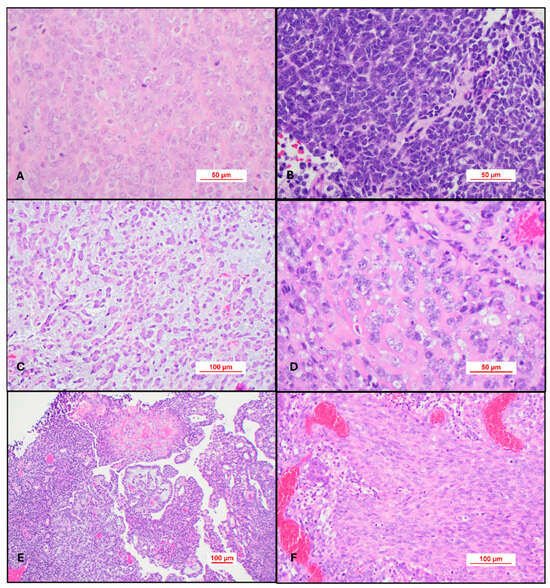

Since their first description by Rorke in 1995, the histogenesis of ATRTs has remained an enigma. Due to the expression of neural, epithelial, and mesenchymal markers, they likely derive from pluripotent fetal cells. Based on genetic and DNA methylation status and transcriptome profiles, ATRTs are further divided into three distinct molecular subgroups: ATRT-SHH, ATRT-TYR, and ATRT-MYC; further subclassifications have also been proposed. The WHO Classification of CNS tumors has included ATRTs in “Embryonal Tumors”. ATRTs are distinct from other embryonal tumors in their clinical presentation, tumor location, imaging characteristics, and prognosis. ATRTs often represent a surgical challenge as treatment requires removing a deep-seated large vascular mass from young patients. They are often resistant to conventional chemotherapy. Radiation therapy, which is imperative, raises serious concerns with regard to effects on the developing CNS of young patients. Safe and effective therapeutic measures are urgently needed.